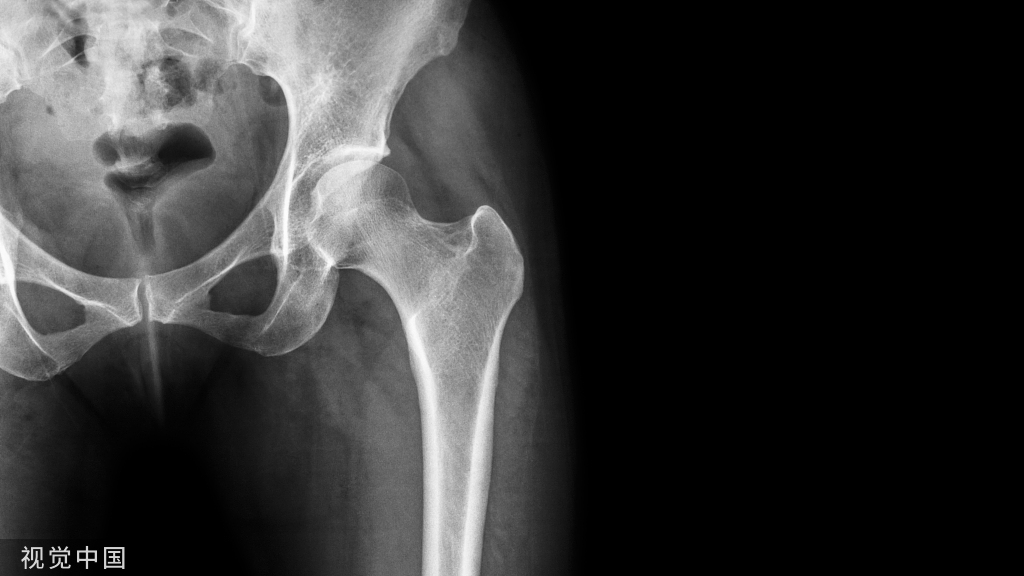

股骨又叫大腿骨,暴力直接打击、从高处坠跌、车辆撞击、碾压等都可造成股骨骨折。发生股骨骨折时,下肢不能活动,骨折处严重肿胀、疼痛,还可出现扭曲或成角等畸形,有时可出现下肢长度缩短。如同时有开放性伤口,则病情更加严重,常会使患者发生休克。

股骨是全身最大的骨头,骨折后如不及时处理,可引起患者大出血、神经损伤等严重并发症,所以必须迅速正确地进行固定包扎,然后立即送往医院处置。